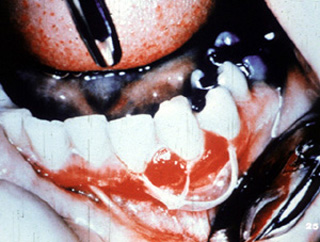

Aquí hay  áreas de ulceración y descamación gingival.

También pueden afectarse otras áreas del mucosa oral. Este señor presenta ulceraciones dolorosas de los mucosa bucal y labio. El examen clínico reveló  úlceras superficiales irregularmente formadas.

En otra vista, las lesiones están presentes en la mucosa yugal y la encía edentula.